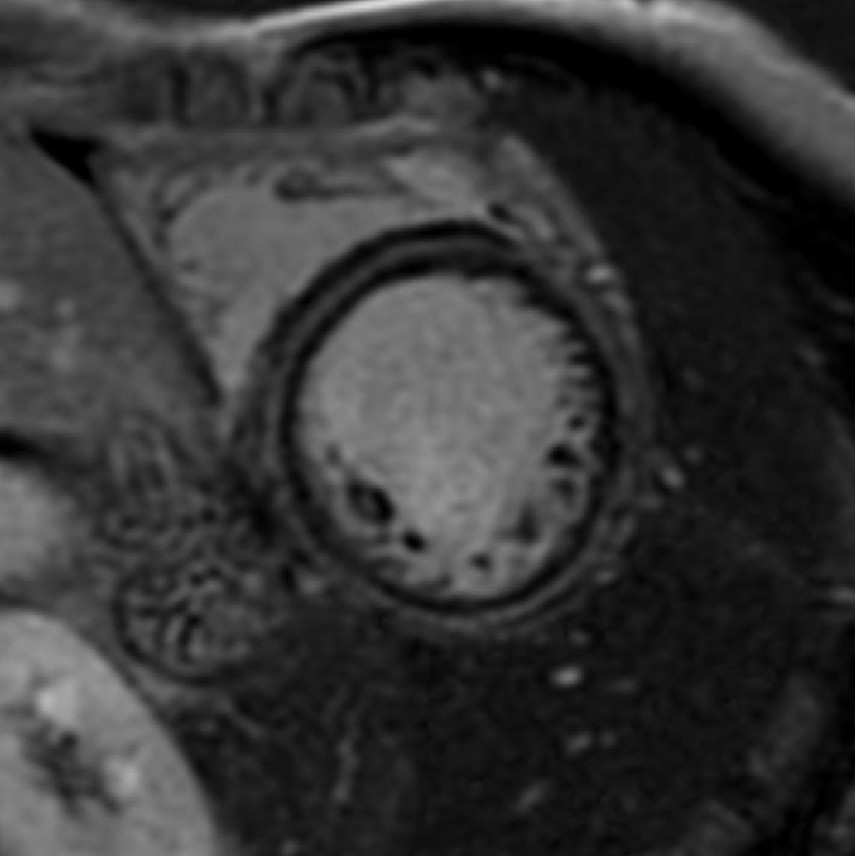

Fifty shades of grey

Caso condiviso da Marcello De Santis